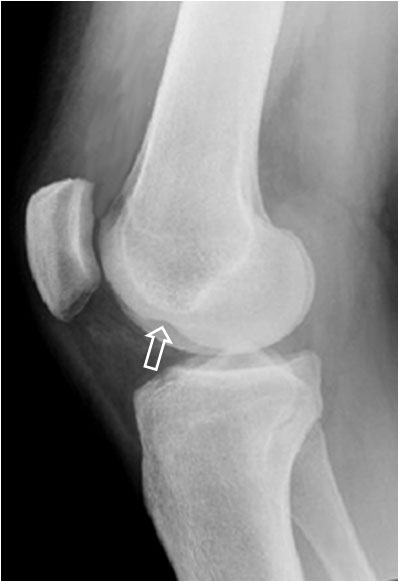

SIGNO DEL SURCO FEMORAL LATERAL

Signo indirecto de rotura del ligamento cruzado anterior (LCA) en la radiografía simple. Se trata de una depresión anormalmente profunda del surco cóndilo-patelar lateral o surco femoral lateral (flecha). Este surco es una pequeña depresión normal en la superficie articular del cóndilo, entre la curvatura que articula con la rótula y la que gira sobre la tibia. El surco anormalmente profundo se produce en la fractura osteocondral impactada, que acontece al tiempo que la rotura del LCA, ya que el mecanismo de ambas lesiones es el mismo: rotación de la articulación y valgo forzado, en el que chocan el platillo tibial contra el cóndilo femoral.